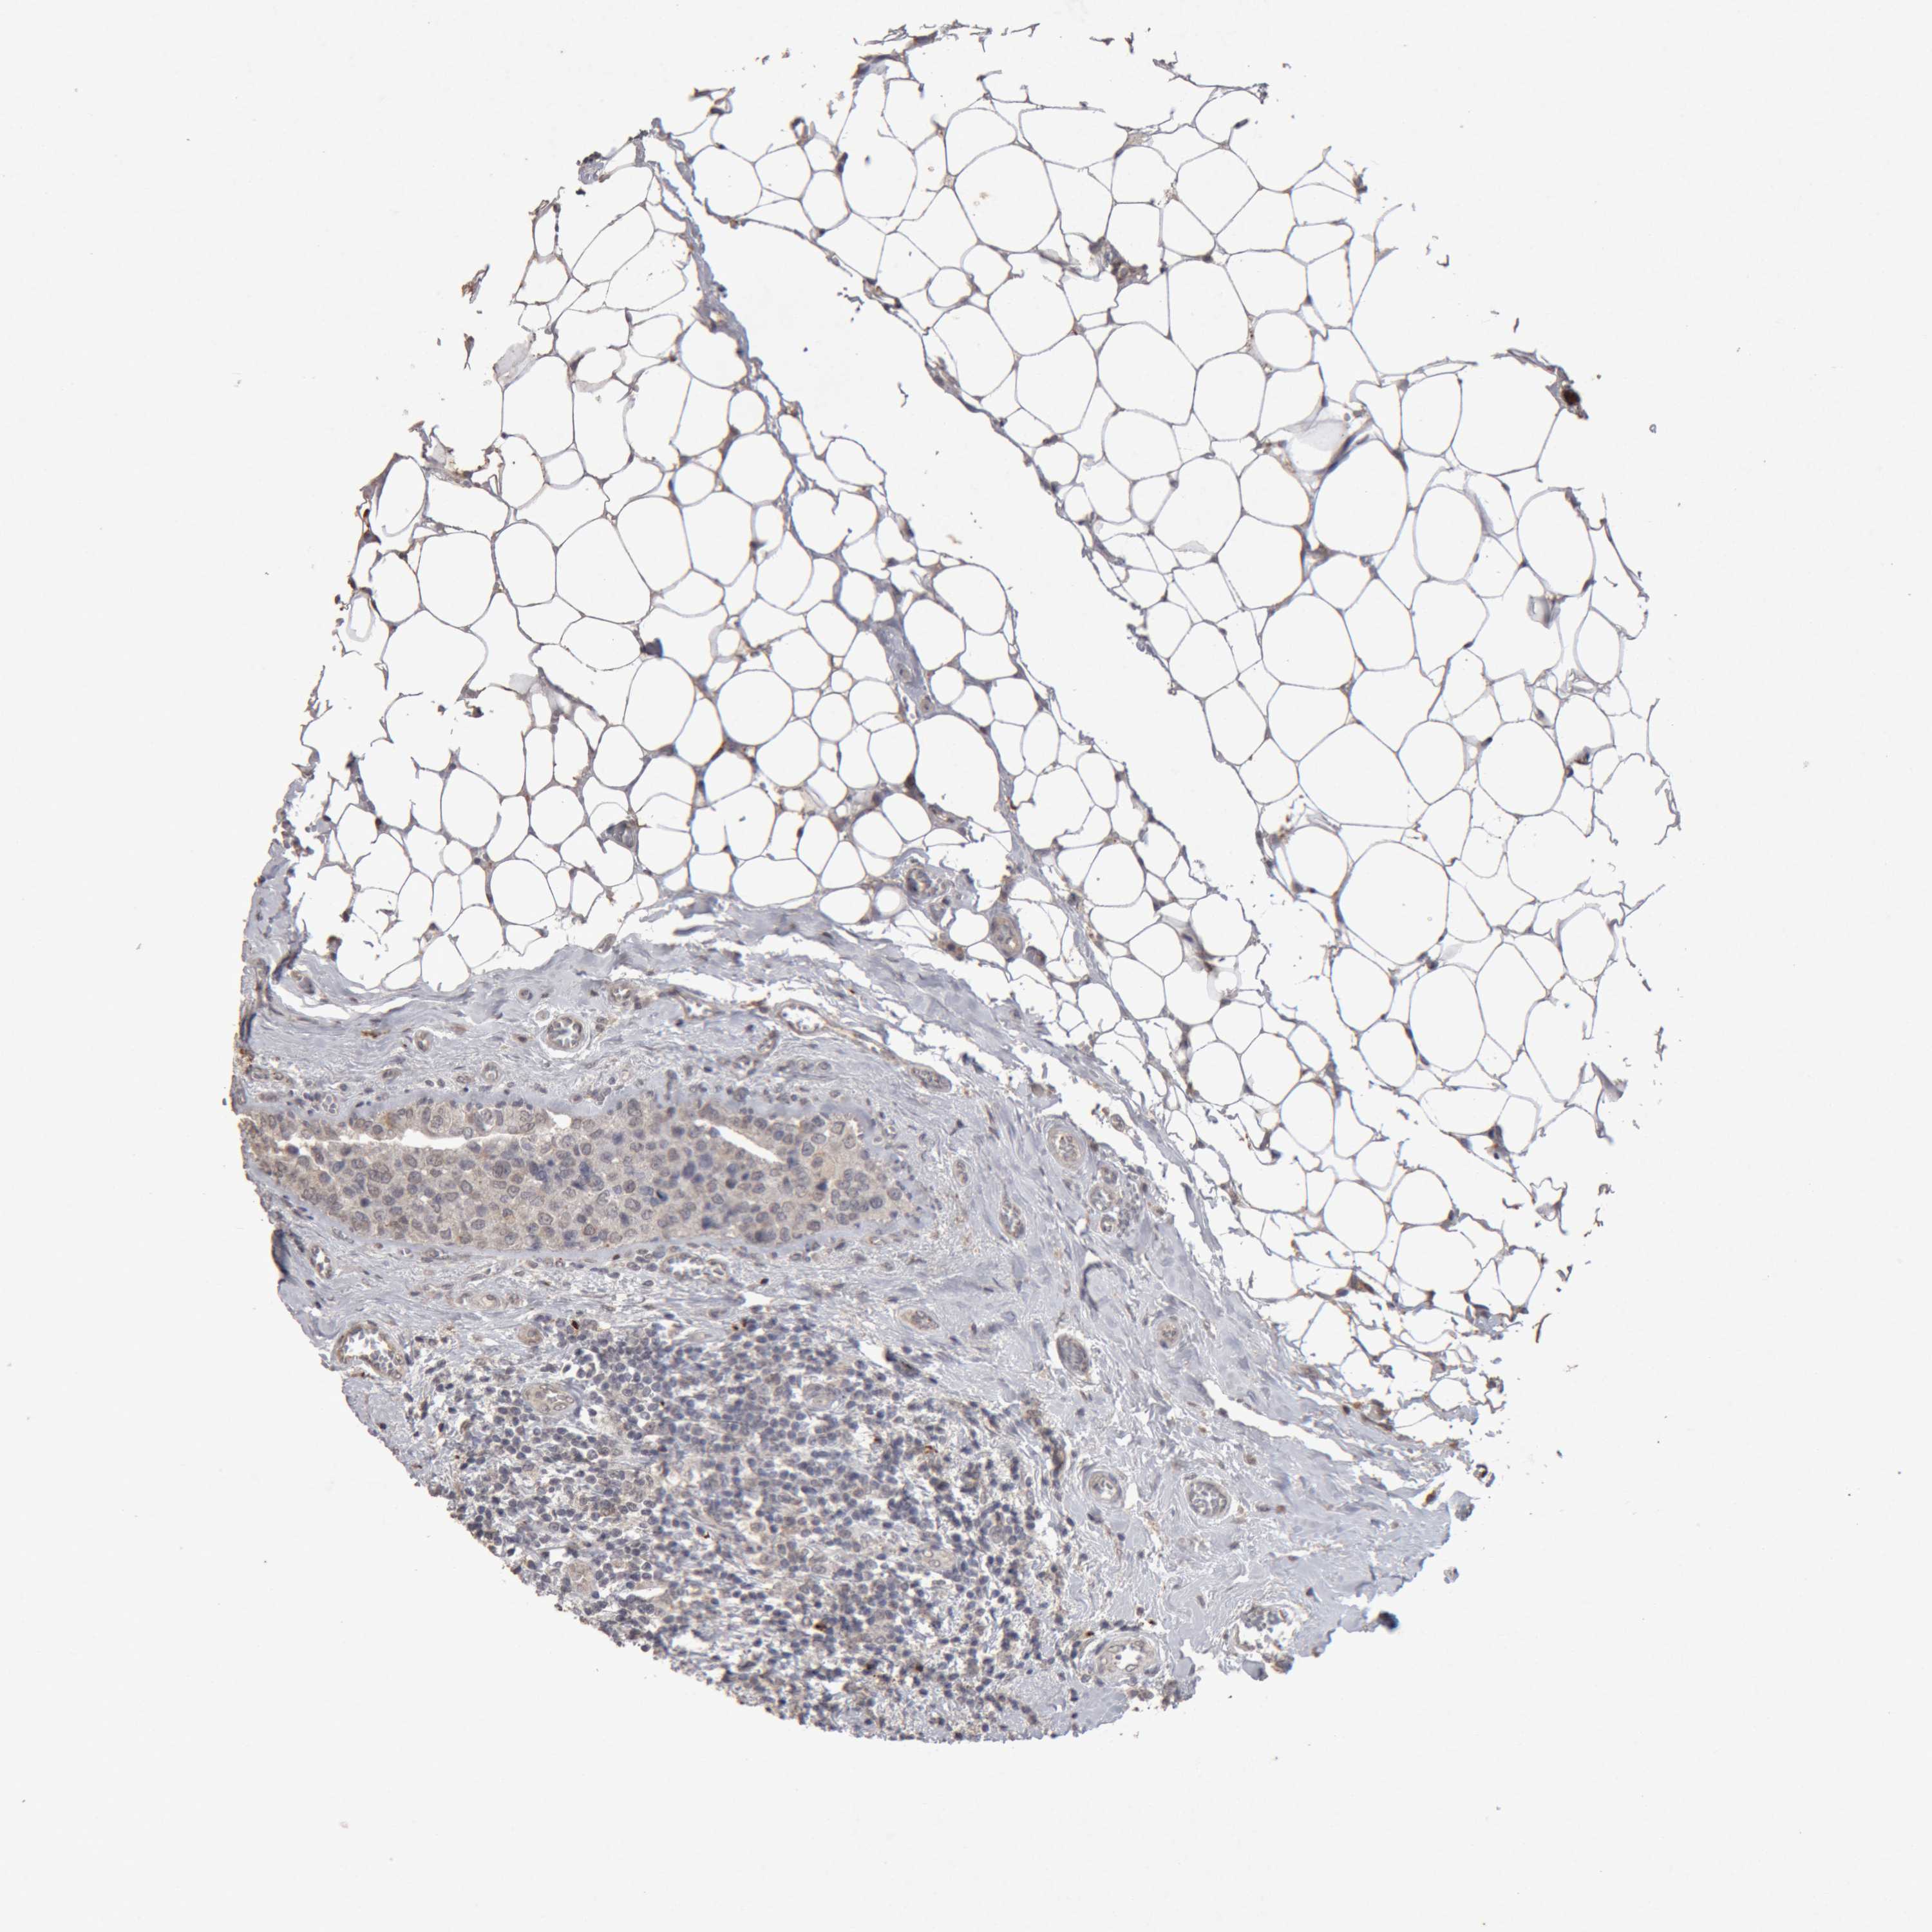

CANCER BREAST CANCER Show tissue menu

BRCA TCGA BRCA VALIDATION PROTEIN EXPRESSION